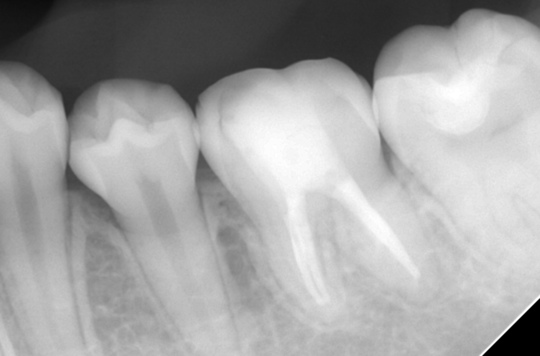

治療後

症状はすべて改善、経過3年後

根の周りが白っぽく骨ができています

骨の穴は完全に消えました